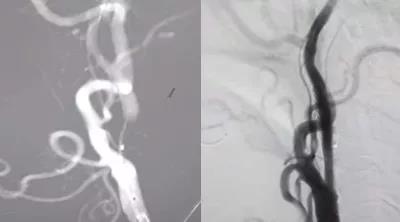

10月27日,在局部麻醉下行介入再通治療,腦血管造影示左側(cè)頸內(nèi)動(dòng)脈起始處閉塞,微導(dǎo)絲攜1.5*2mm球囊多次嘗試,成功通過閉塞段,給予球囊擴(kuò)張,擴(kuò)張后造影見有細(xì)血流通過,保護(hù)傘緩慢通過狹窄段,釋放保護(hù)傘,給予4*20mm球囊再次擴(kuò)張,然后植入閉環(huán)支架一枚,造影示血流通暢,顱內(nèi)血管顯影良好,再通成功,結(jié)束手術(shù),患者無不適,3天后出院。

相對于頸內(nèi)動(dòng)脈狹窄支架植入術(shù),頸內(nèi)動(dòng)脈閉塞再通術(shù)有著更高的風(fēng)險(xiǎn)及手術(shù)難度。閉塞的血管處是一些血栓及斑塊,再通過程中這些血栓和斑塊可能被血流沖入顱內(nèi),一旦發(fā)生這種情況,后果不堪設(shè)想,因此對醫(yī)生的手術(shù)技巧及手術(shù)經(jīng)驗(yàn)要求很高?;颊咝g(shù)后24小時(shí)仍然是危險(xiǎn)期,因?yàn)殚]塞一邊的腦組織長期適應(yīng)了低血流,血管一開通,大量血流涌入腦組織,可能會(huì)因高灌注導(dǎo)致腦出血。所以術(shù)后24小時(shí)應(yīng)嚴(yán)格控制血壓,防止腦出血。該患者術(shù)后在心電監(jiān)護(hù)下嚴(yán)格控制血壓,安穩(wěn)度過了危險(xiǎn)期。由于是微創(chuàng)手術(shù),術(shù)后觀察兩天后已恢復(fù)良好,順利出院。